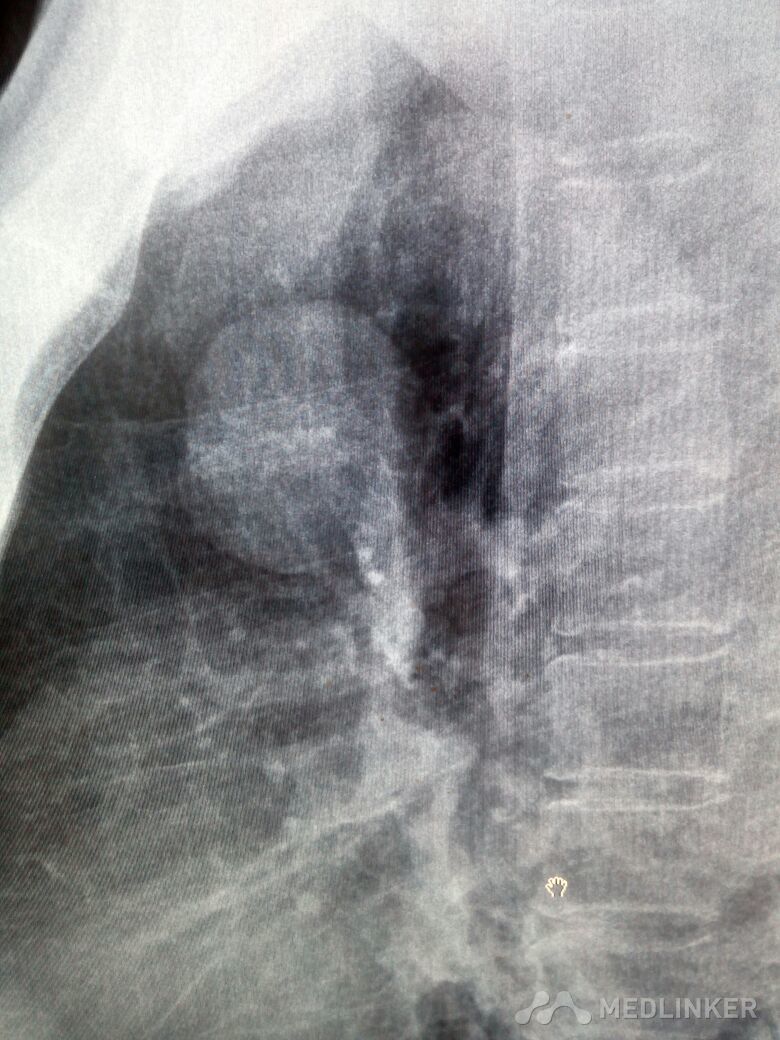

肺内错构瘤一例

患者体检时发现,手术,病理证实错构瘤